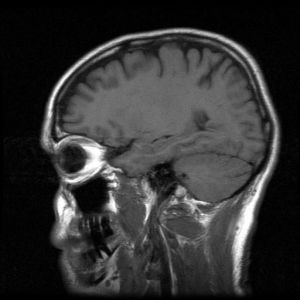

Cvičenie zlepšuje výkonnosť mozgu tvorením nových buniek v tej časti mozgu, ktorá zodpovedá za pamäť a jej strácanie sa. Tvrdia to americkí vedci na základe skúmania tohto procesu u myší.

Pamäť ovplyvňuje vek, u väčšiny ľudí začína pamäť klesať zhruba po tridsiatke. Vplyv cvičenia na časť mozgu zvanú hippocampus vedci zisťovali testami na myšiach, pomocou magnetickej rezonancie. Tú použili tiež pri skúmaní mozgu ľudí pred a po cvičení.

Našli rovnaké vzorky zobrazenia, z čoho usúdili, že ľuďom tiež rastú nové mozgové bunky, keď cvičia. Nijaký predchádzajúci výskum neskúmal tak systematicky rôzne časti hippocampu a nešpecifikoval tú časť, ktorú najväčšmi ovplyvňuje cvičenie, uviedol vedúci výskumu, neurológ Scott Small.

Závery štúdie uverejnil odborný časopis Proceedings of the National Academy of Sciences (PNAS). Vedci zistili, že u myší môže cvičenie spôsobiť vývoj nových mozgových buniek. Na meranie krvného objemu mozgu použili magnetickú rezonanciu.

Nemohli, prirodzene, pitvať mozgy ľudí, aby videli, či rastú nové neuróny. Pomohla im magnetická rezonancia. U 11 zdravých dobrovoľníkov, ktorí sa podrobili trojmesačným cvičeniam aerobiku, merali tiež hladinu kyslíka pred a po tréningovom programe.

Cvičenia zvyšovali mozgový prietok krvi. Podobnosti medzi zmenami u myší a ľudí, ktoré vyvolalo cvičenie v mozgovom krvnom objeme v hippocampe, viedli vedcov k názoru, že efekt vzniká podobným mechanizmom.